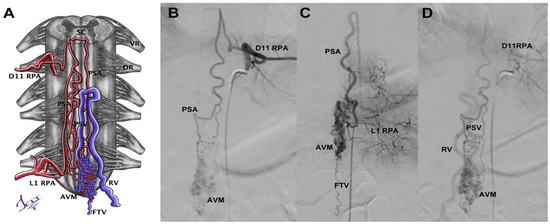

3.5.3. Case 8

| Case 8 | 26/F | 2 episodes of syncope, chronic headache | 1 | Type V perimedullary CCJ AVF (Hiramatsu)/epidural dorsal (Geibprasert) | Posterior meningeal arteries, PSA, and radiculomeningeal branch from V3 on the left side | 2 small ostia at foramen magnum | 2 arterial aneurysm | Venous drainage to marginal sinus–epidural plexus | Embolized with Histoacryl in 2 sessions | Almost complete occlusion, without neurological deficit | 0 |